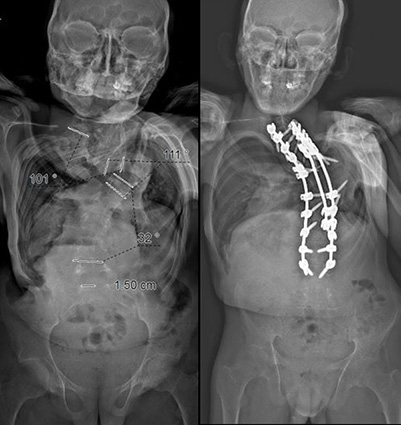

Case Study Neurofibromatosis and Thoracic Kyphoscoliosis

A 23-year-old male who had neurofibromatosis and severe thoracic kyphoscoliosis complained of back pain and some shortness of breath along with preoperative right leg pain in his posterior thigh and calf. He presented with some lower extremity weakness and a spastic gait. The patient was in halo gravity for two months for a severe deformity greater than 180 degrees of kyphoscoliosis. Following the halo traction, the patient was treated with a posterior spinal instrumentation and fusion from T1-L4 and is now doing well.

BeforeAfter